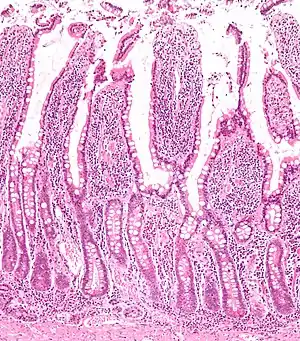

![]() Micrograph of the small intestine mucosa showing the intestinal glands - bottom 1/3 of image. H&E stain. | |

In histology, an intestinal gland (also crypt of Lieberkühn and intestinal crypt) is a gland found in between villi in the intestinal epithelium lining of the small intestine and large intestine (or colon). The glands and intestinal villi are covered by epithelium, which contains multiple types of cells: enterocytes (absorbing water and electrolytes), goblet cells (secreting mucus), enteroendocrine cells (secreting hormones), cup cells, tuft cells, and at the base of the gland, Paneth cells (secreting anti-microbial peptides) and stem cells.

Structure

Intestinal glands are found in the epithelia of the small intestine, namely the duodenum, jejunum, and ileum, and in the large intestine (colon), where they are sometimes called colonic crypts. Intestinal glands of the small intestine contain a base of replicating stem cells, Paneth cells of the innate immune system, and goblet cells, which produce mucus.[1] In the colon, crypts do not have Paneth cells.[2]